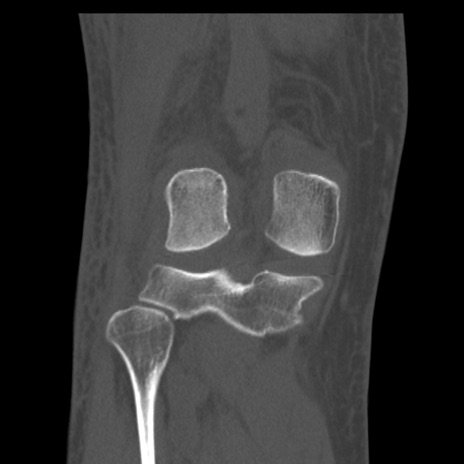

症例28 右膝関節CT(冠状断像)

右膝関節CT